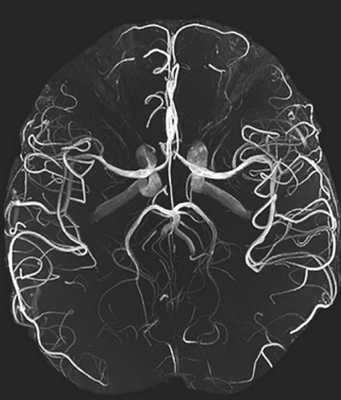

3D-модель церебральных артерий и вен

На фоне ядерного резонанса возникает слабый электромагнитный сигнал, который считывают при помощи чувствительных детекторов. Информацию обрабатывают, данные преобразуют в серию послойных снимков и транслируют на монитор компьютера.

МРТ сосудов головного мозга включает сканирование вен и артерий, изучение характера церебрального кровоснабжения. Объект исследования обладает выраженными парамагнетическими свойствами. Благодаря высокому содержанию воды жидкие среды обеспечивают гиперинтенсивный сигнал на фоне окружающих тканей. При необходимости МРТ артерий головного мозга можно проводить без использования контраста.

С помощью магнитно-резонансной томографии получают подробные изображения всей артериальной системы головы или определенного участка интракраниального пространства. На снимках хорошо видны сосуды и окружающие ткани.